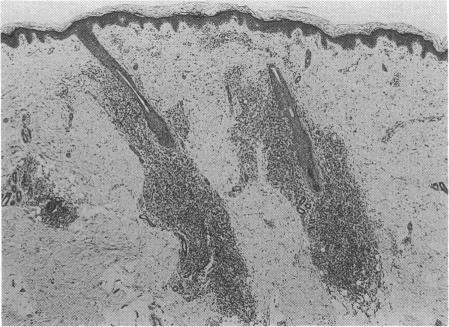

Chronic rash associated with congenital rubella.

J R Soc Med. 1994 Apr;87(4):242-3.

PMID:8182685

Skin dimples and rubella.皮肤酒窝与风疹。

Congenital rubella syndrome. Unusual cutaneous manifestations.先天性风疹综合征。不寻常的皮肤表现。

Dermal erythropoiesis in neonatal infants. A manifestation of intra-uterine viral disease.新生儿皮肤造血。宫内病毒病的一种表现。

Letter: Chronic rashes in congenital rubella: isolation of virus from skin.信函:先天性风疹中的慢性皮疹:从皮肤中分离出病毒。